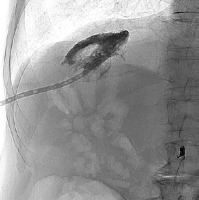

One month after surgery, the patient again presented with fever and chills. Imaging studies demonstrated a hepatopleural fistula (Figure 4). Due to the patient’s refusal of surgery, percutaneous drainage was performed. Repeated exchanges of the drainage were required over the following 3 years (Figure 5). The patient remained free of disease progression but ultimately died due to cardiovascular causes 3.4 years after RL.

Figure 4

A – Contrast-enhanced CT coronal plane showing hepatopleural fistula. B – Contrast-enhanced CT axial plane showing hepatopleural fistula with fluid and gas